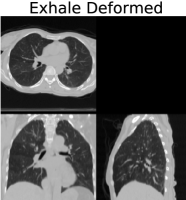

We applied our proposed weighted density registration algorithm to the first subject from the DIR dataset. This subject has images at 10 timepoints and has a set of 300 corresponding landmarks between the full inhale image and the full exhale image. These landmarks were manually chosen by three independent observers. Without any deformation, the landmark error is 4.01 mm (SD 2.91 mm). Using our method, the landmark error is reduced to 0.88 mm (SD 0.94 mm), which is only slightly higher than the observer repeat registration error of 0.85 mm (SD 1.24 mm).

We implement our algorithm on the GPU and plot the energy as well as the Fisher-Rao metric with and without applying the deformation. These results are shown in Figure 6. In this figure, we show that we have excellent data match, while the deformation remains physiologically realistic: inside the lungs there is substantial volume change due to respiration, but the deformation outside the lungs is volume preserving. With a voxel dataset, our algorithm takes approximately nine minutes running for four thousand iterations on a single nVidia Titan Z GPU.